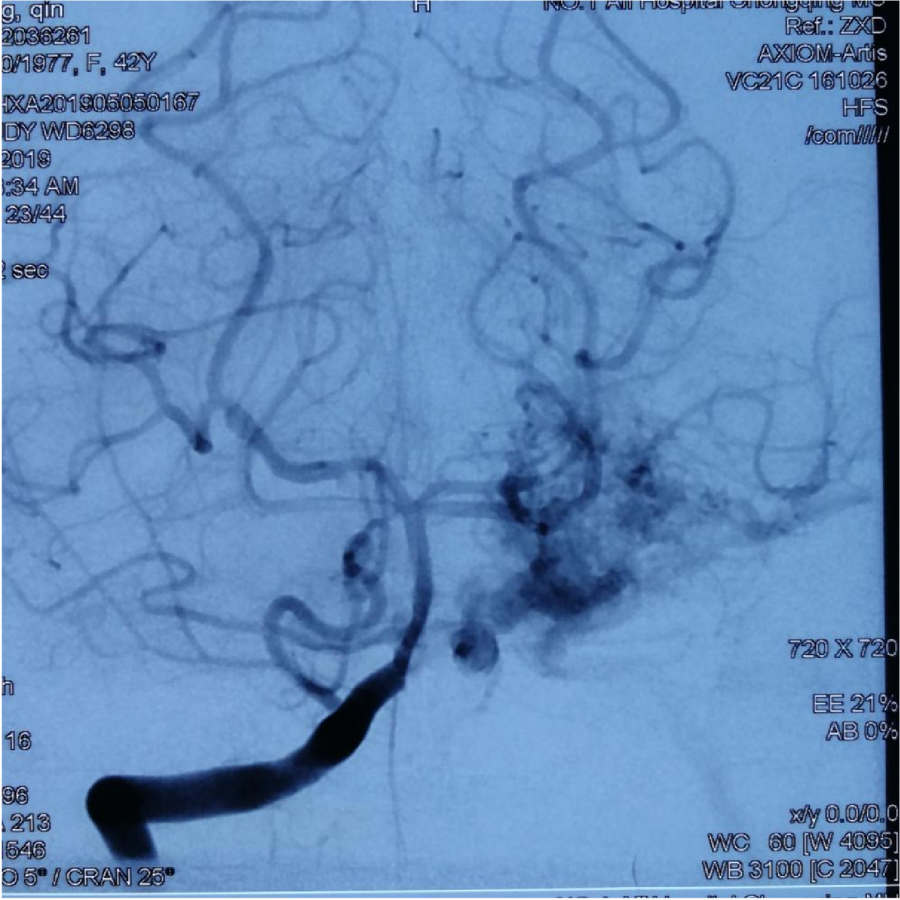

本次⼊院⾏DSA检查:PICA供⾎区有畸形⾎管团,引流到横窦

1、患者1年前⾏接⼊栓塞治疗,现仍有出⾎,且DSA显⽰PICA供⾎区仍有⼤量机型⾎管 团。